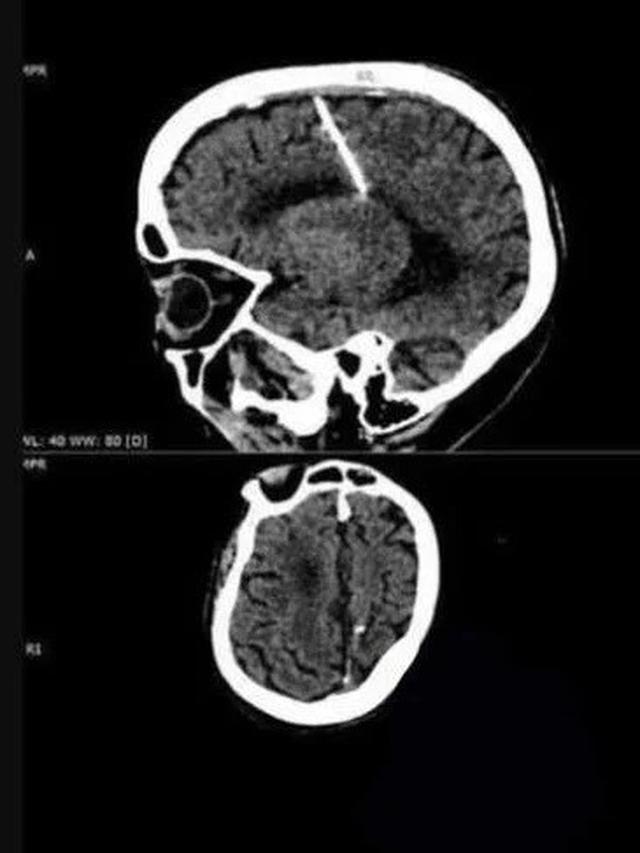

Liputan6.com, Jakarta Seorang wanita berusia 80 tahun dari wilayah Sakhalin, Rusia, baru-baru ini membuat penemuan yang mengejutkan setelah menjalani CT scan. Hasil pemeriksaan tersebut mengungkapkan adanya jarum logam berukuran 3 cm yang tertancap di sisi kiri otaknya.

Kementerian Kesehatan Sakhalin telah merilis foto hasil CT scan wanita tersebut, yang disertai dengan penjelasan yang membingungkan. Mempertimbangkan usia wanita tersebut, para dokter meyakini bahwa jarum tersebut dimasukkan ke dalam otaknya oleh orang tuanya sendiri segera setelah dia dilahirkan.

“Kasus seperti ini sering terjadi pada tahun-tahun kelaparan: sebuah jarum tipis dimasukkan ke dalam ubun-ubun bayi, sehingga merusak otak,” kata Kementerian Kesehatan setempat mengutip dari MKRU Sakhalin.

Mereka akan memasukkan jarum tipis ke dalam otak bayi melalui ubun-ubun, yaitu celah di tengkorak yang secara bertahap menutup seiring pertumbuhan bayi. Tujuannya tak lain untuk membunuh mereka. Metode ini tidak meninggalkan jejak, karena ubun-ubun menutup dengan cepat, tidak meninggalkan bukti adanya indikasi pembunuhan.

"Ubun-ubun segera menutup, menyembunyikan jejak kejahatan, dan bayinya meninggal,” lanjut keterangan Kementerian Kesehatan Sakhalin

Namun, yang lebih mencengangkan adalah bahwa wanita tersebut tidak pernah mengalami sakit kepala yang signifikan akibat benda asing di otaknya. Jika bukan karena CT scan baru-baru ini, dia mungkin tidak akan pernah mengetahui keberadaan jarum tersebut.